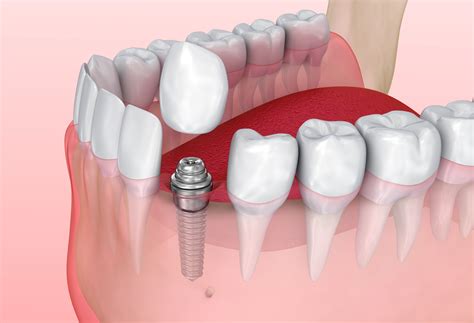

Implant Placement

Once the patient is deemed a suitable candidate, the dentist will surgically place the titanium implants into the jawbone. This procedure is typically performed under local anesthesia, and the implants are allowed to heal and integrate with the bone over a period of several months.

Abutment Placement

After the implants have fully integrated with the bone, the dentist will place an abutment on top of each implant. The abutment serves as a connector between the implant and the prosthetic tooth or teeth.